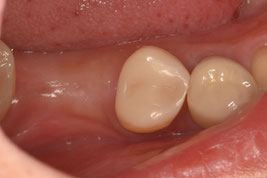

軸面の健全歯質を大幅に残したうえで、オーバーレイの形態で修復しました。インジェクションモールディング法を応用しております。直接修復なので、海外からの来院であっても、短期滞在で対応可能です。

コア部分にグラスファイバー繊維を含有したエバーXフロー(GC)を用いております。エバーXフロー(GC)を使用するようになってから、修復物の破損が圧倒的に少ない!特にダイレクトブリッジの破折が目を見張るほどに減少しました!技術の向上に感謝です。

インジェクションモールディング法を用いて、ダイレクトクラウンにて完了させました。ファイバーコアによる支台築造と同時にダイレクトクラウンを成形するため、歯根・築造体・クラウンとが一体化したモノブロック構造で強度を担保できます。ファイバーコアからダイレクトクラウンまで一気に進めて、だいたい2時間の施術時間です。施術中にドクターが離れることができないのですが、圧倒的な時間短縮です。

エバーXフロー(GC)は従来のコンポジットレジンよりも硬いわけではありません。硬質フィラー含有量が少ないので、むしろ柔らかいのです。柔らかく、そして良くしなるため、割れないのです。

右下4番の治療を希望されて、1年ぶりに来院してくれました。問題なく良好に経過しているとのことで、とても安心しました。